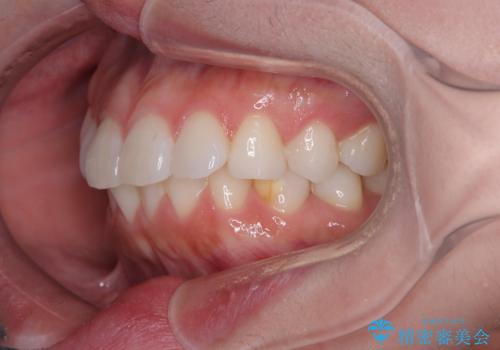

- 上下前歯の叢生を気にして来院された患者様です。

軽度な叢生であり、安価で短期間の治療を規模されていたため、インビザライン・モデレートを用いて矯正治療を行うこととしました。